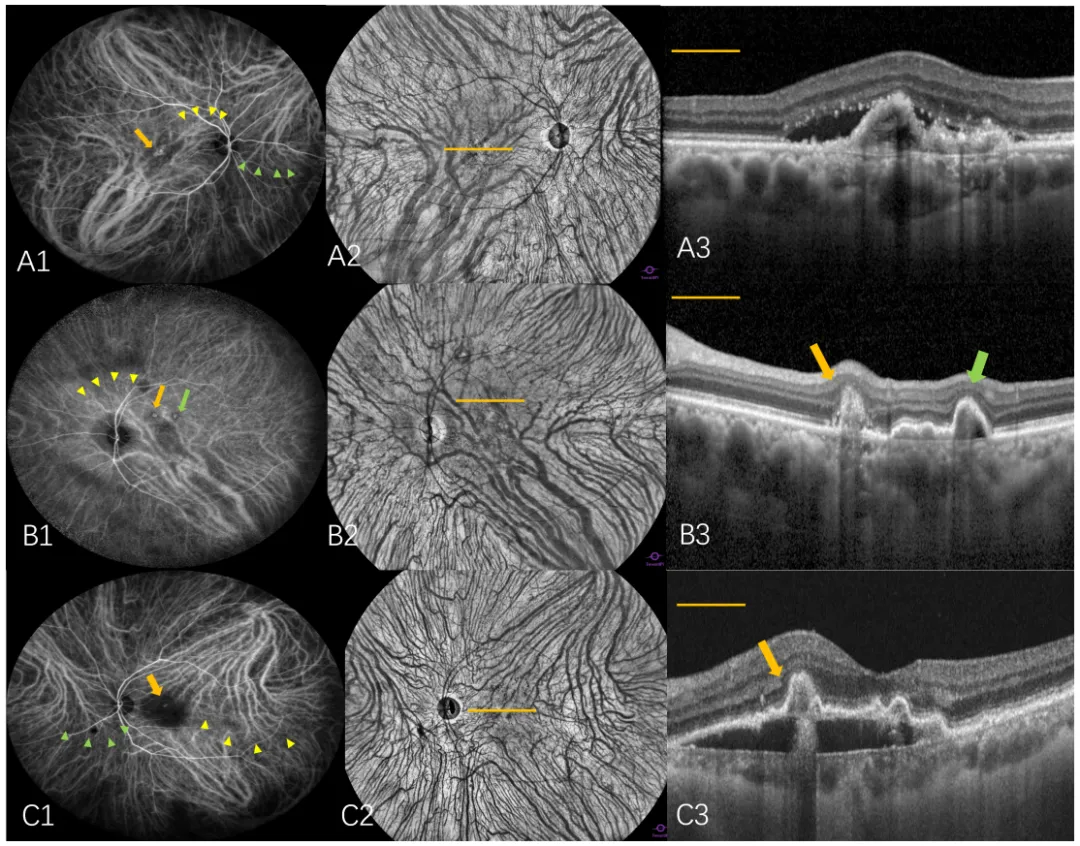

图1. 通过使用WF-ICGA和en face OCTA可视化非对称性优势VV和优势VV区域内的息肉状病灶。(A1–A3) 在PCV眼中上方鼻侧(SN)和下方颞侧(IT)区域观察到两个优势VV。下方颞侧VV远端(黄色箭头)横跨黄斑区,上方鼻侧VV末端(绿色箭头)横跨视盘。一处息肉状病灶(橙色箭头)位于下方颞侧(IT)优势VV区域内,被归类为1型MNV。(B1–B3) 在 PCV 眼的下方颞侧(IT)区域存在一个优势VV,其远端(黄色箭头)横跨黄斑区。两个息肉状病灶分布在下方颞侧(IT)优势VV区域内,尽管其形态学表现提示位于上方颞侧(ST)象限,但被归类为位于下方颞侧(IT)象限。一处息肉状病灶被归类为混合1型和2型MNV(橙色箭头),另一处病灶被归类为1型MNV(绿色箭头)。(C1–C3) 在 PCV 眼中上方鼻侧(SN)和上方颞侧(ST)区域识别出两个优势 VV。上方颞侧(ST)优势 VV 远端(黄色箭头)横跨黄斑区,上方鼻侧(SN)优势 VV 末端(绿色箭头)横跨视盘。 一处息肉状病灶(橙色箭头)位于上方颞侧(ST)优势VV区域内,并被归类为位于上方颞侧(ST)象限内。C3 处显示的息肉状病灶(黄色箭头)被归类为混合型1型和2型MNV。